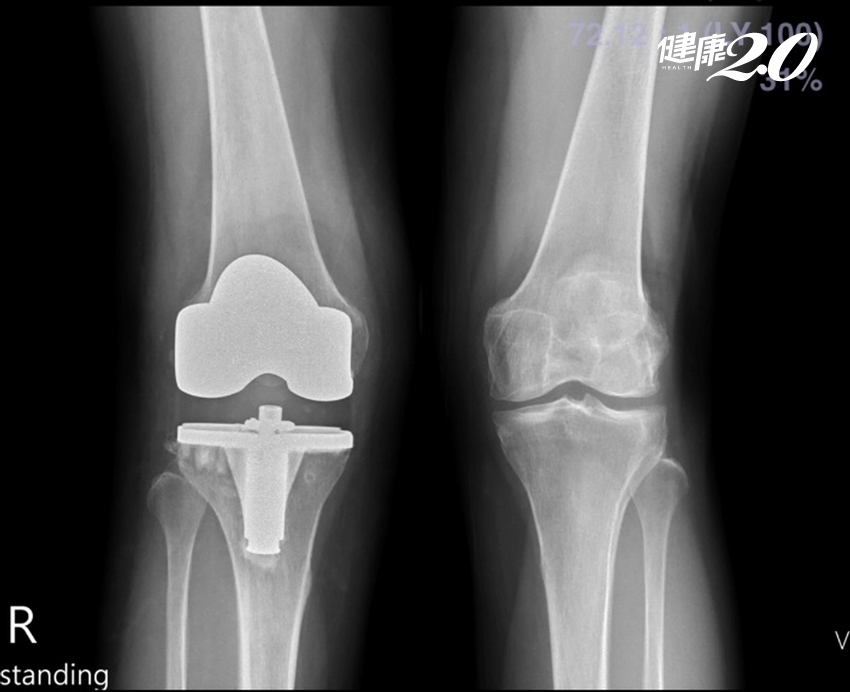

嚴重的膝外翻病患可選擇第二代人工膝關節即「髁骨限制性人工膝關節」,可增加術後穩定度,但膝關節後續併發症機率較第一代高,活動度也不如第一代理想,所以必須謹慎評估,最後陳阿姨是使用第一代人工膝關節置換。

▲術後,已可明顯看出矯正的幅度。